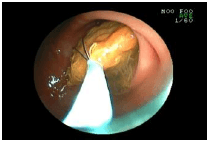

2. 胃の中のヒモを取り出した例

![]() |

ヒモを飲み込んでしまった猫の胃の内視鏡画像です。 ヒモが胃の中で絡まっているのが見えます。(矢印) |